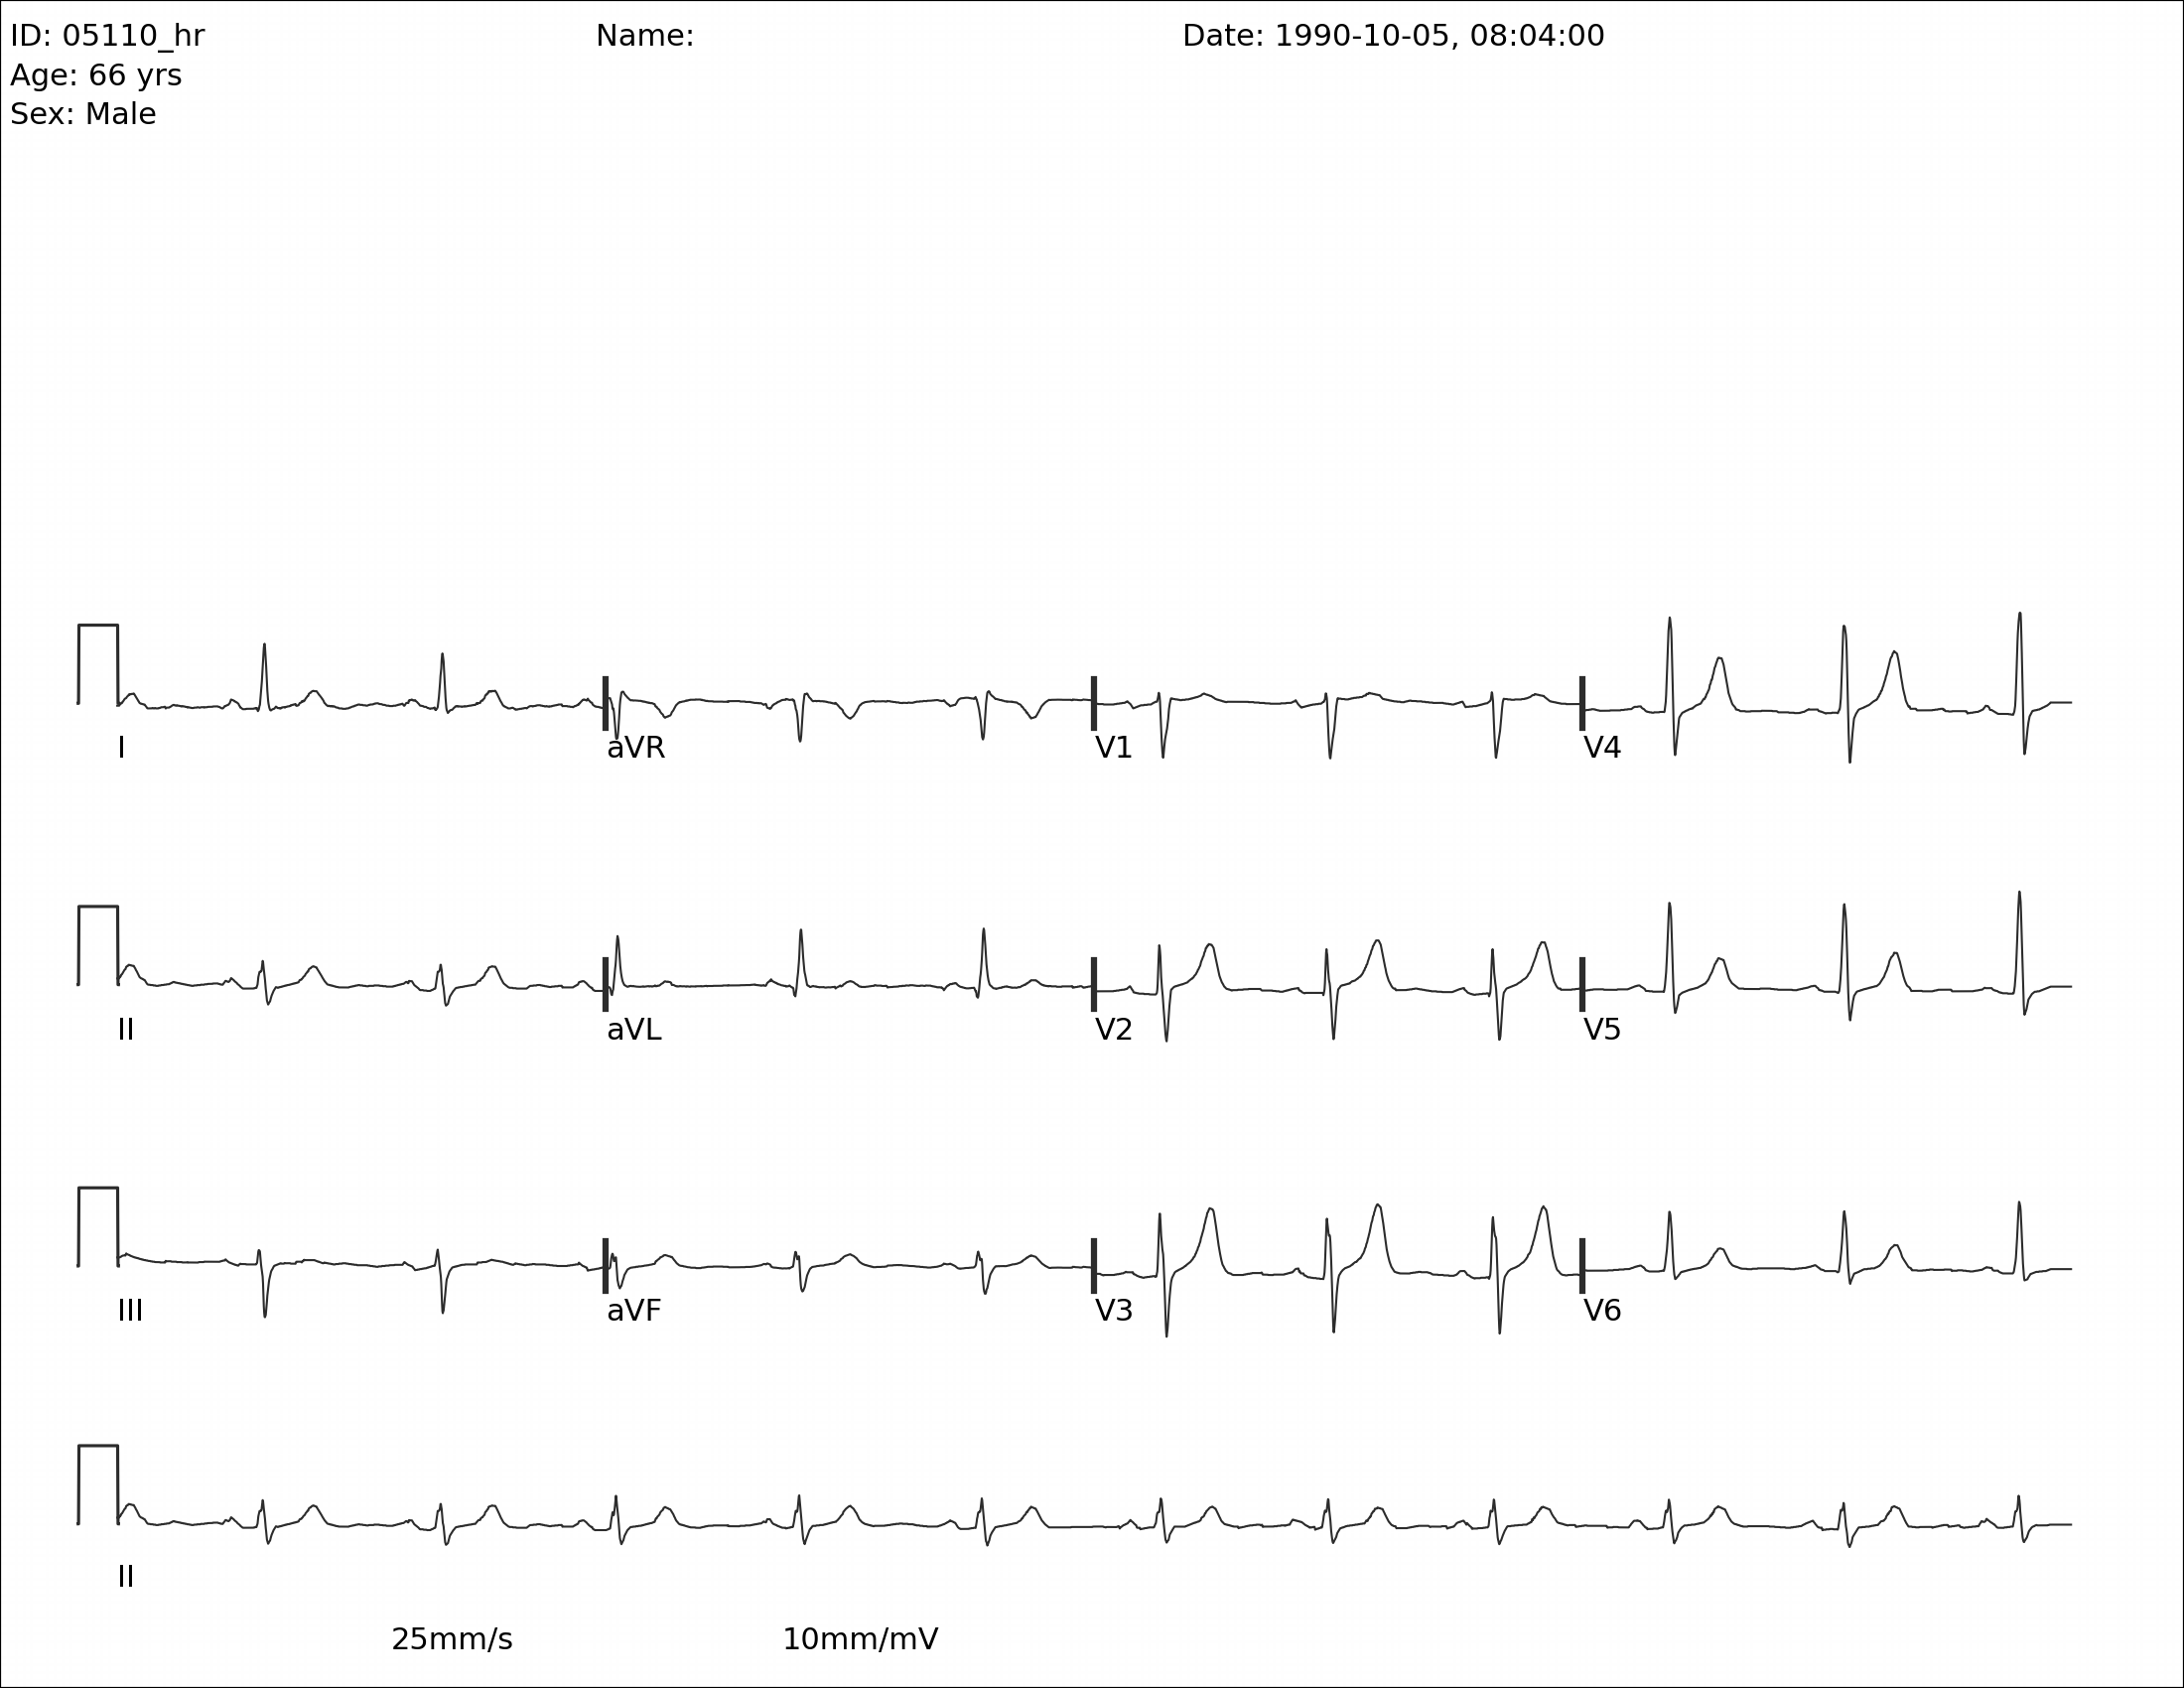

I occasionally peruse available Kaggle competitions to see if there’s something fun to explore. This week, I came across this competition around converting EKG images into time series data. This piqued my interest because context can give such a big advantage over a pure ML approach. I’m going to walk through some basics of EKGs and hopefully we can extract some time series data without using any ML. That said, there is obviously a place for computer vision to do a lot of the work that I’m going to write more deterministic code for.

For this, we’re going to go back to the red channel. We’ll use our previous analysis that we used to find rows that have no signal, and instead use it to find the rows that have our signals. There are 4 rows of signals. The first three have all 12 leads, and the bottom row is lead II going all the way across to be used for rate and rhythm.

Now we’ve found the parts of the image that have signal and we also identified the zero voltage line. Technically, zero voltage is defined as the voltage between the T wave and the following P wave, but this approximation of counting dark pixels in each row and identifying a local maximum seems to work incredibly well. You’ll notice that the bands are labeled 5-8 because I started at the top and each section of text or signal created a band. This will not always be consistent. In lead II, you can see that the label is a new band, but in the other rows, the label is included in the band. Depending on the patient, the device, and the strength of the lead connection, the amplitude of the signal can vary and overlap with the label (sometimes even overlap with the signal above or below).